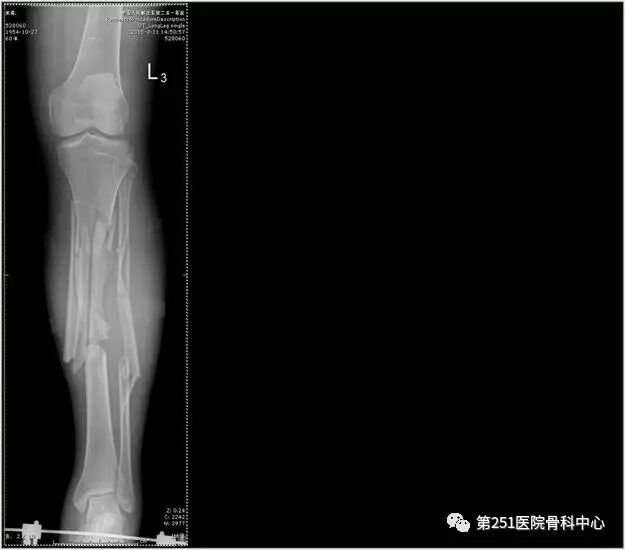

病例1:男性,40岁,车祸伤,胫腓骨多段骨折。

![]()